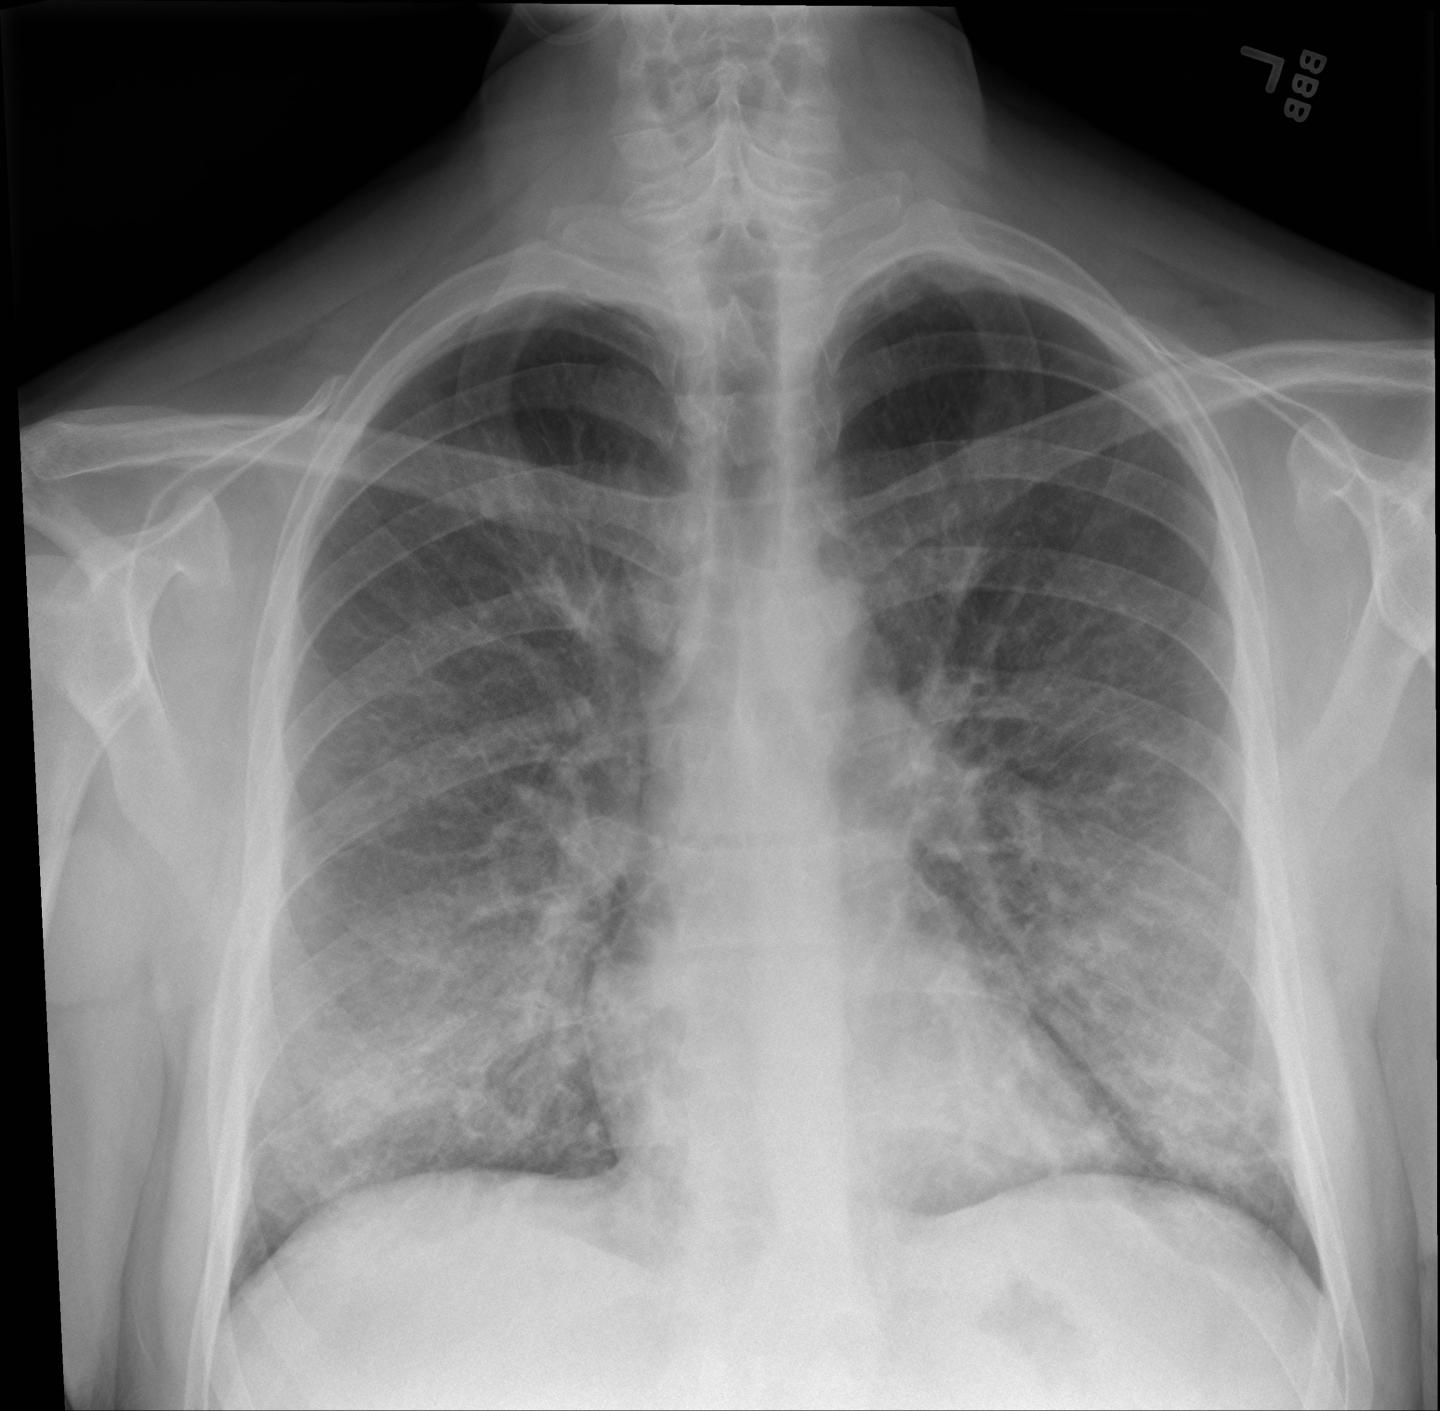

In the study, Intermountain Healthcare researchers identified 60 E-VALI patients at 13 different Intermountain hospitals or clinics in Utah from June 27, 2019, through October 4, 2019. The diagnosis was defined by a history of vaping or e-cigarette use within 90 days prior to symptoms, abnormalities shown in chest imaging, and no other cause for these findings (such as pneumonia).

In the first study to report follow-up findings for these patients, Intermountain clinicians performed a short follow-up exam after two weeks and found that, although most patients had improved significantly, many had residual abnormalities. Only 23 percent of the patients still needed supplementary oxygen, but most still showed some signs of lung abnormalities on their imaging and breathing tests.

These findings are helping physicians recognize what lung injuries associated with e-cigarettes or vaping look like -- and helping them maintain a high degree of suspicion when they diagnose lung injuries in patients who've been vaping.